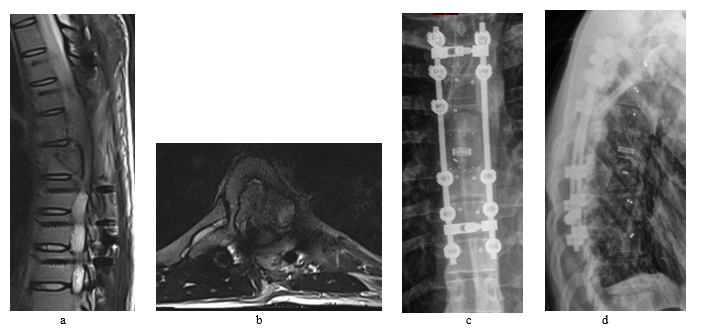

Follow up MRI and CT scans 4 months after the second surgery had revealed aggressive recurrence of the tumor invading nearby tissue and displacing the cord to the left (Figure 5). No metastatic deposits had been found so far on the follow up scans.

Adjuvant radiation therapy (50 Gray in 25 sessions) had been started after recovery and completed in mid-August/2023. Follow up post radiation CT scans showed continuing tumor growth.

Figure 5: Despite all efforts fighting the tumor, follow up images shows recurrence of the tumor that aggressively invading the nearby structures. The MRI was performed 4 months after the second surgery (a + b). CT scans (c + d) were performed after the adjuvant radiation treatment, 7 months from the second surgery.

At time submitting this article, patient was receiving chemotherapy MAP (methotrexate [M] doxorubicin [A] and Cisplatin [P]) that has started in October/2023 with few treatments related side effects and generalized deconditioning. Neuro exam so far is as baseline. No clinical and radiographical evidence so far that chemotherapy and radiotherapy are treating the tumor or controlling its progression.